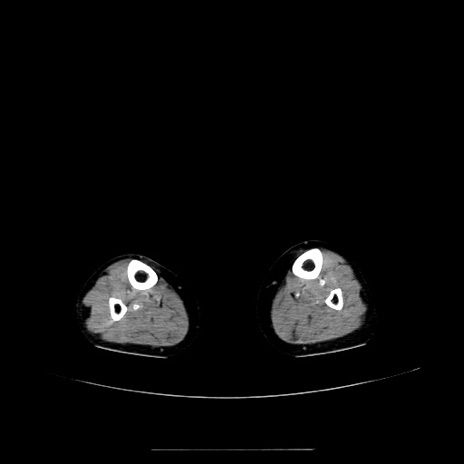

【症例】70歳代女性

【主訴】お腹が張る

【現病歴】1週間くらい前から腹部膨満の自覚あり。昨日夜から増悪したため、本日救急外来受診。

【身体所見】意識清明、BT 36.5℃、BP 165/106mmHg、HR 80bpm、SpO2 98%、腹部:膨満、軟、自発痛・圧痛なし、触診にて不快感あり、腸蠕動音:減弱

【データ】WBC 12600、CRP 1.04